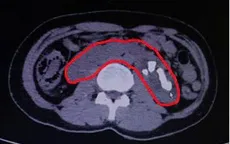

Một bệnh nhân mắc thận móng ngựa bẩm sinh hiếm gặp

VTV.vn - Bệnh viện đa khoa tỉnh Hà Giang vừa phẫu thuật thành công cho bệnh nhân Chảo Páo Toan (28 tuổi, trú tại Tả Lủng, Mèo Vạc, Hà Giang) mắc thận móng ngựa bẩm sinh.